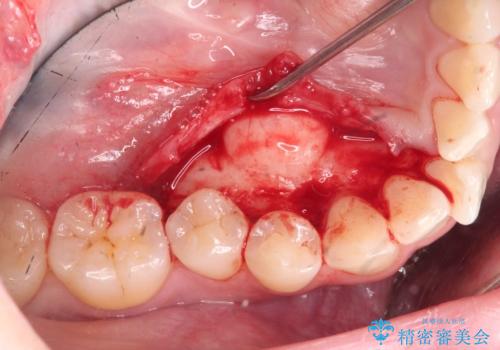

上下の歯のがたつきを改善するマウスピース矯正治療と、下顎に見られる大きな骨隆起を外科的に除去する治療計画を進めていきます。

骨隆起の除去は、静脈内鎮静法を用いてほとんど記憶のないうちに行うことができます。

歯並びが改善したとともに、骨隆起を除去したことで舌をしまうスペースも増え安定した口腔内環境を確立することができました。

外科処置の注意事項(リスク・副作用など)

- 外科手術のため、術後に出血、痛みや腫れ、違和感を伴います